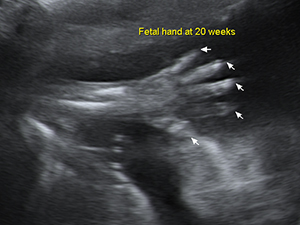

懷孕20週的胎兒手掌